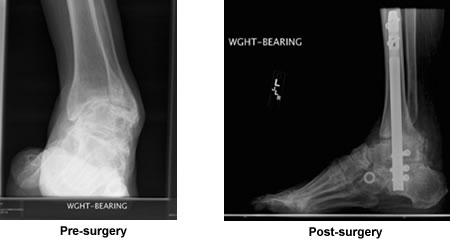

Muscular Dystrophy Foot Reconstruction

In July, 2008, I met Dr. Kenneth Leavitt at his office at New England Baptist Hospital. My left foot had been deformed since birth du e to Muscular Dystrophy. For the previous five years I could not walk 50 feet without excruciating pain. He took some x-rays, told me exactly what he was going to do, and how long I would be laid up. After three surgeries, I walked out of rehab with the help of crutches.

Last month I walked two miles on long beach in Gloucester without pain, something that I love, but had not been able to do in six years. Thanks to Dr. Leavitt and his colleague Dr. Talmo.